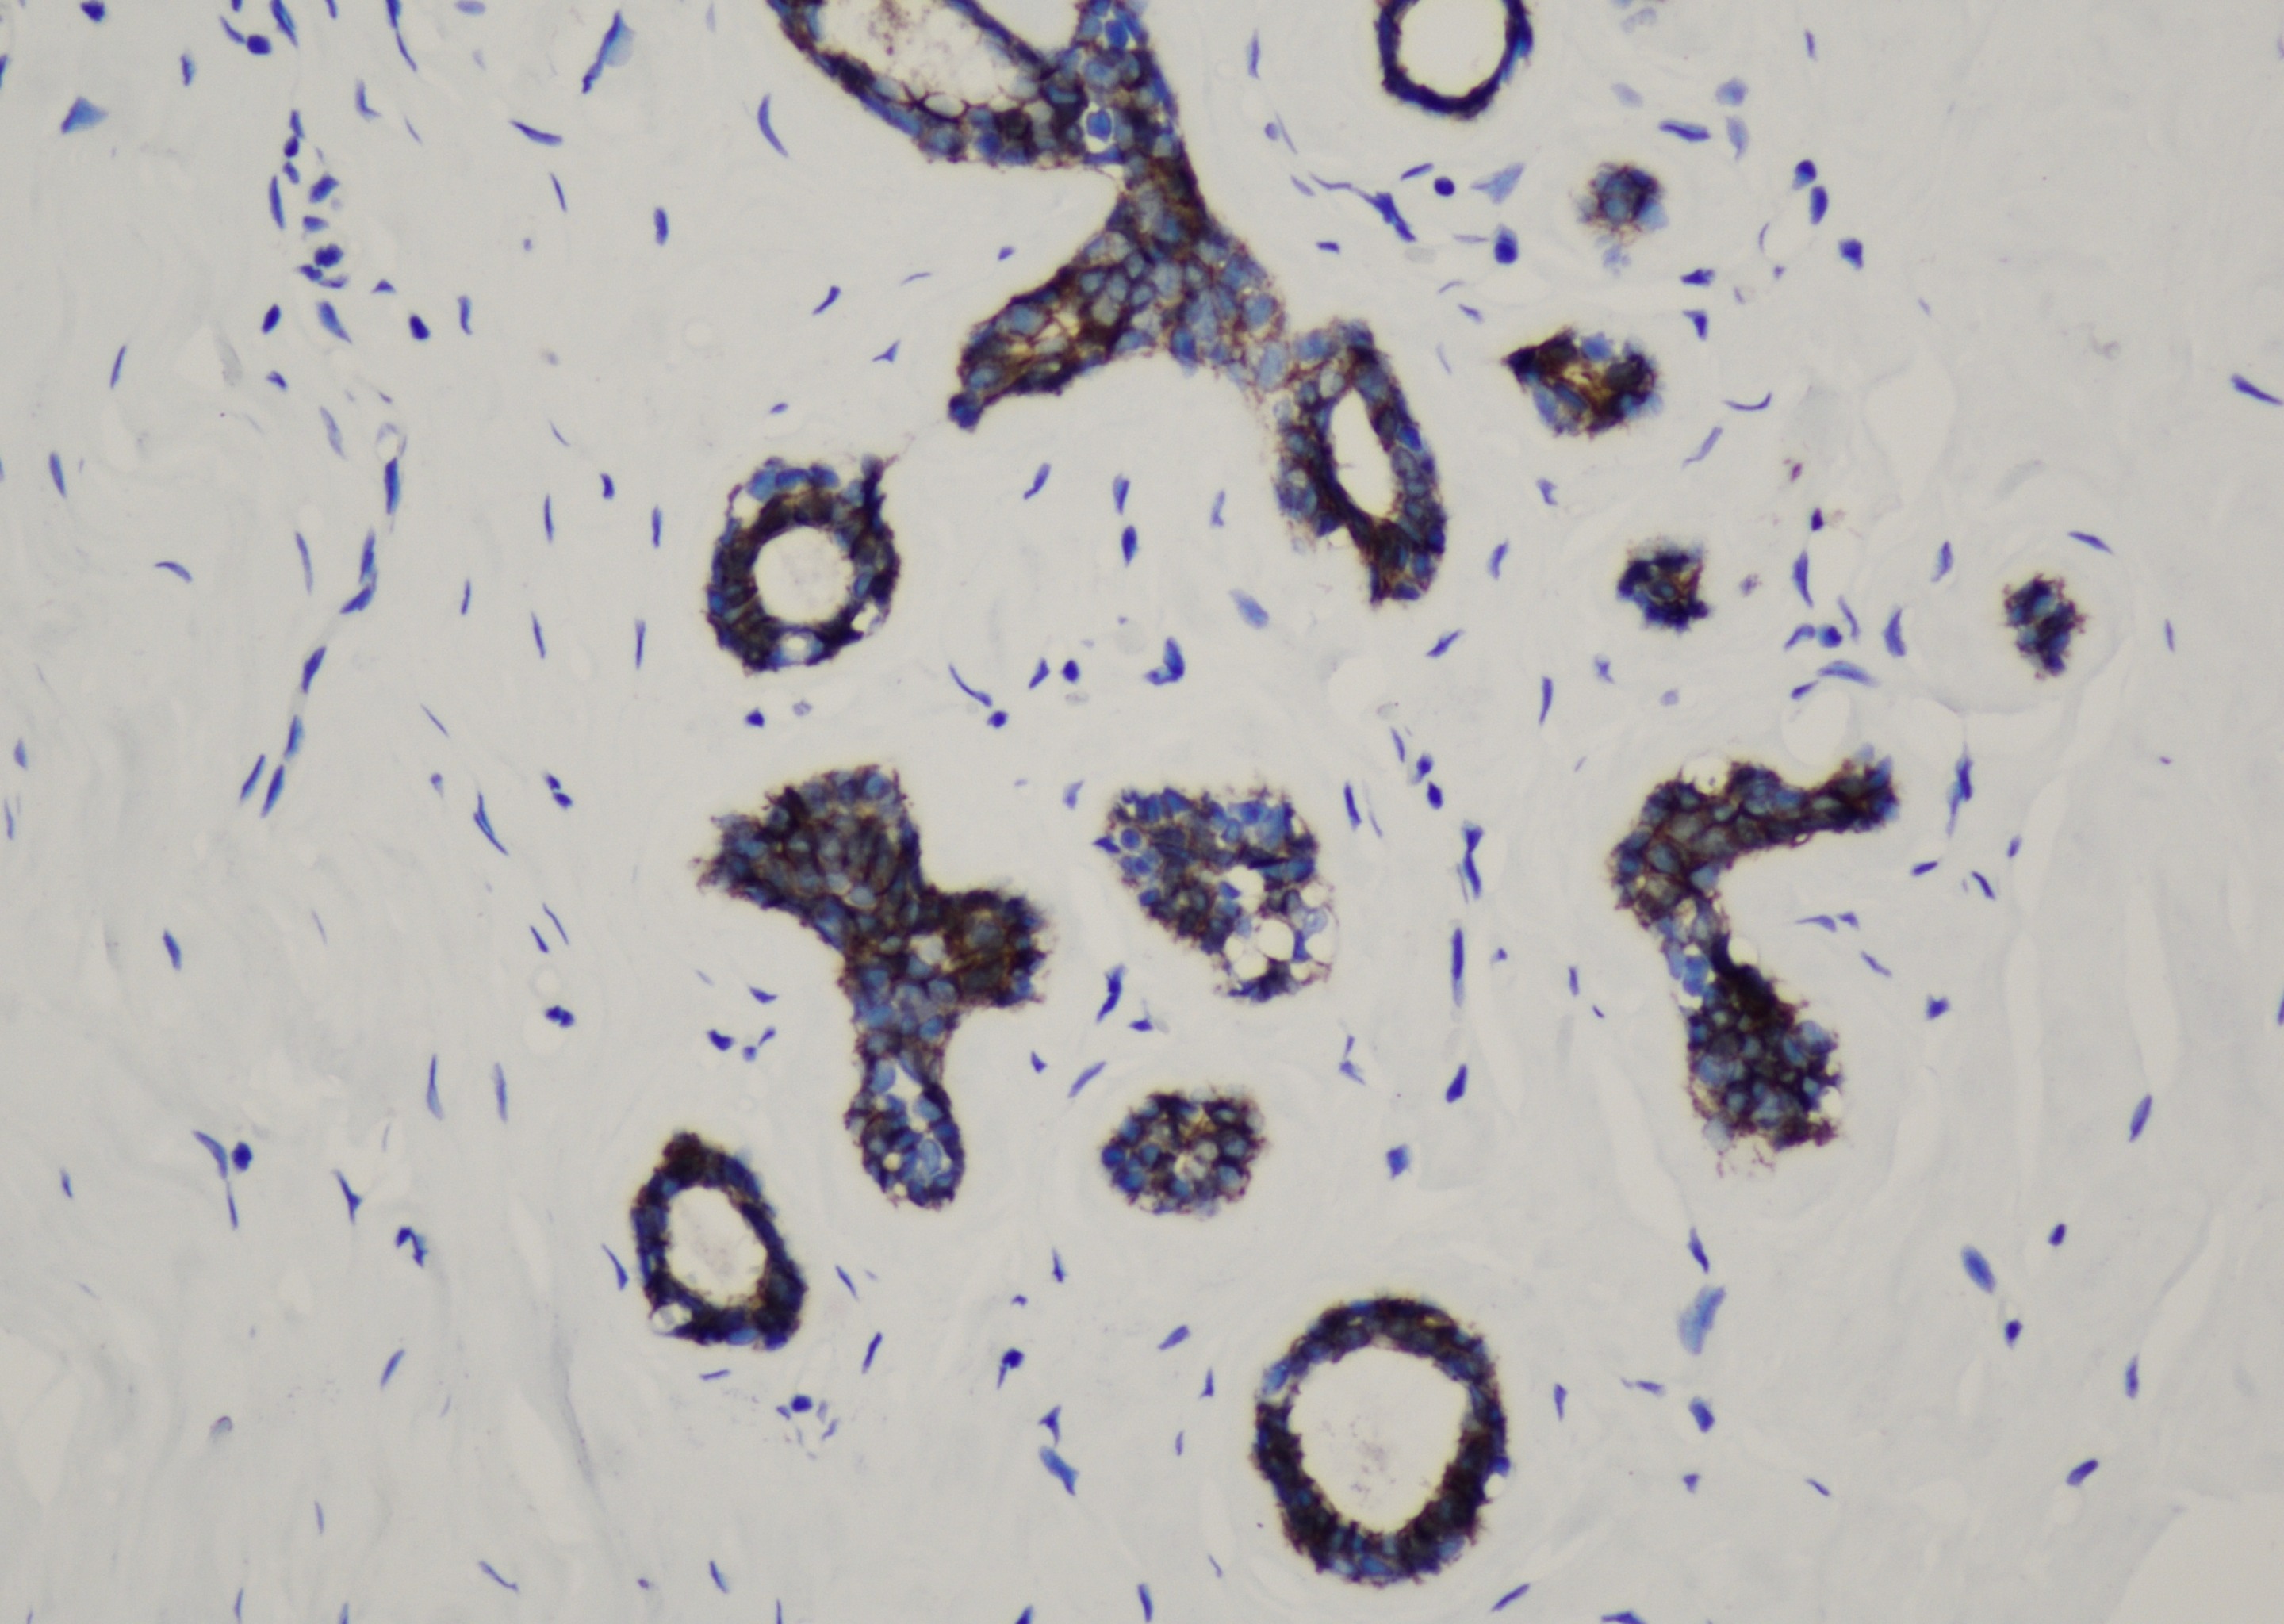

Annexin A1

Annexin A1(膜联蛋白A1)是钙依赖磷脂结合蛋白家族成员,分子量为37kDa。可与磷脂结合蛋白相互作 用以促进膜融合进一步参与胞吐,静息状态下主要存在于细胞质中,与肿瘤的发生有关,在细胞膜、质和部分 细胞核表达阳性。Annexin A1可用于毛细胞白血病的诊断、胃腺癌的诊断及预后判断。

| 细胞定位 | 细胞质/膜 |